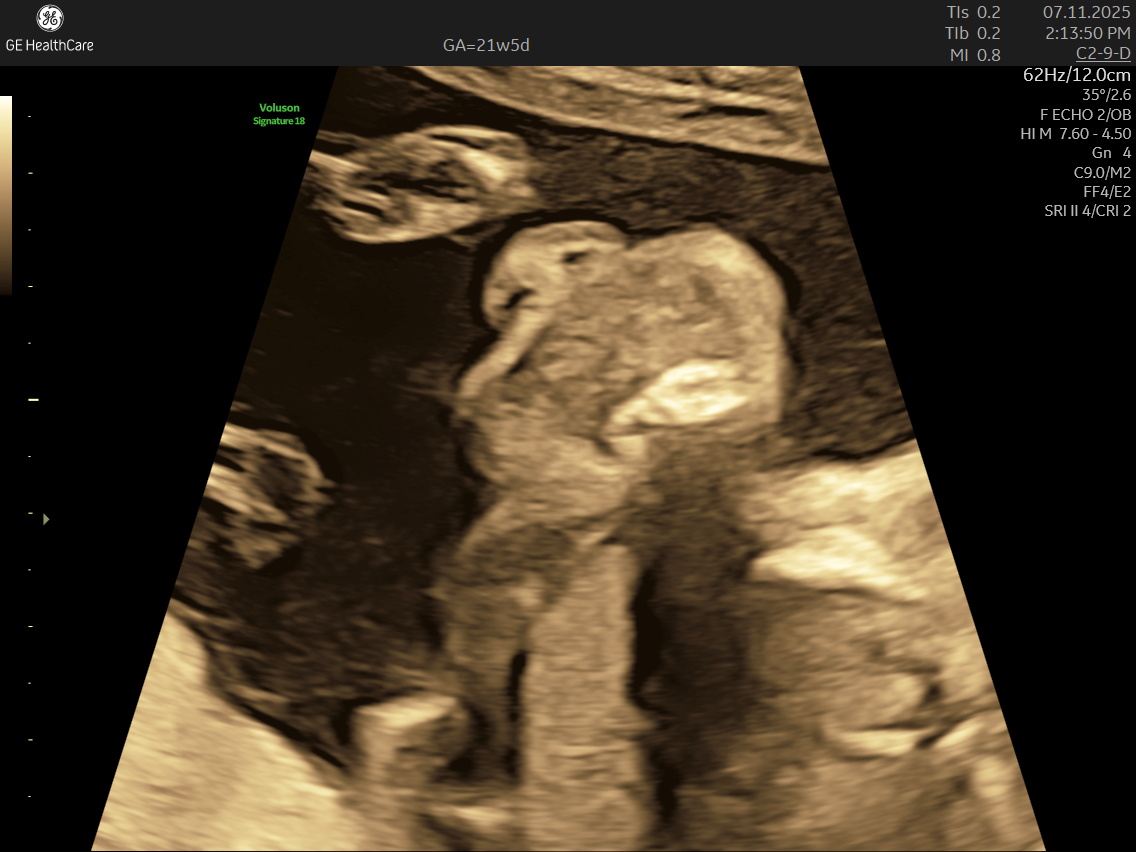

• Face: Checks the eyes, lips, and nose, ruling out conditions like cleft lip/ palate.

• Face: heck the eyes, lips, and nose, ruling out conditions like cleft lip.

IMAGE GALLERY